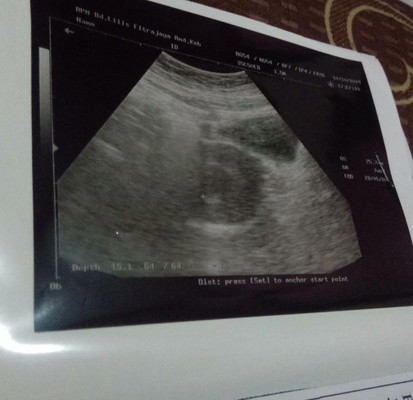

USG

Bunda mohon berbagi pengalamannya donk... Usia kandungan saya sekarang 7 minggu jalan ke 8 minggu, kemarin saya disuruh USG oleh bidan dan hasilnya katanya kantong janinnya sudah terlihat tapi janinnya masih kecil dan blm terlihat, akhirnya saya diberi utrogestan penguat kandungan...kira2 biasaya usia kandungan berapa minggu bunda janin itu bisa terlihat?? Tolong masukannya dari bunda-bunda